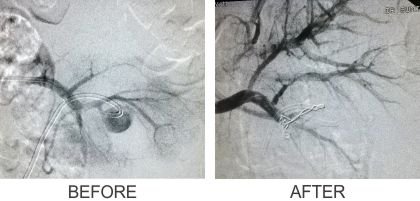

1. Coil Embolisation

5. Renal Aneurysm Coiling